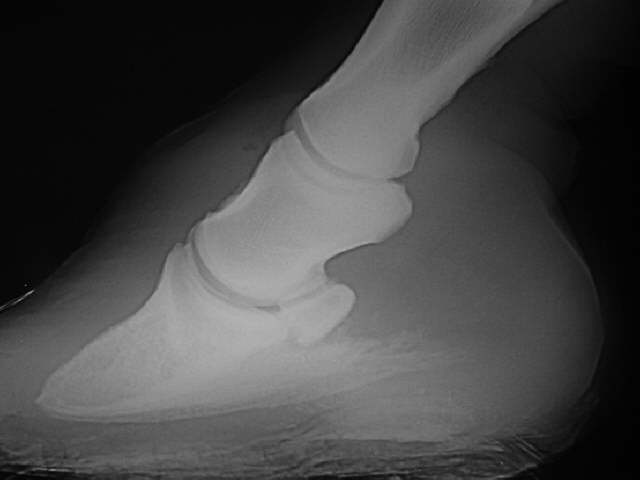

Flacher Huf